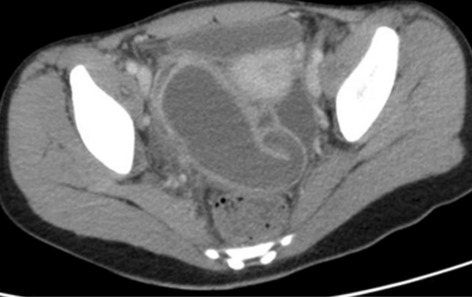

Gallstones are a common gastrointestinal disease that can have major complications and can affects up to 20% of patients in Europe, becoming a major public health problem. The most common complication of gallstones is acute cholecystitis (AC). Among patients presenting to the Emergency Service Unit (ESU) with acute abdominal symptoms, acute cholecystitis is found in approximately 3–9% of cases.

Aims: To identify the peculiarities of the management of AC with medium and severe forms, in the Covid19 pandemic period compared to the period before the pandemic.

Methods: A retrospective, comparative study was performed of moderate and severe cases of AC (according to the Tokyo 2018 guideline classification) presented in the ESU of Constanta County Hospital, Romania and hospitalized in the General Surgery Department between March-November 2020 and the similar period of 2019.

Result: The comparative analysis of the data shows a decrease in the number of presentations in ESU of AC cases during the pandemic, compared to the previous year, most often due to patients' fear of contacting the virus in the hospital environment. The median time between the onset of symptoms and the presentation in the ESU: 2020 – 14 days, 2019 – 5 days. Forms of moderate and severe AC predominated in the pandemic: GradeI—14.28%; GradeII—57.14%; GradeIII—28.57%. In 2019 GradeI—66.39%, GradeII—27.73%, GradeIII—5.88%. Laparoscopic cholecystectomy was attempted for all patients from the beginning, but the complications identified during surgery and severe forms led to a conversion rate in 2020 of 14.28%, compared to 5.88% in 2019. The severity of the cases is also observed in the postoperative complications encountered (perihepatic abscess Fig. 2. Figure 2, wound infection, bile leak; 2019—5.04%, 2020—23.21%), which required surgical reinterventions to solve them (2019: 2.52%, 2020: 10.71%). The number of deaths was significantly higher in 2020 (5.35%), compared to 2019 (0.84%).

Conclusion: Neglecting this pathology frequently encountered in ESU can lead to life-threatening complications and therefore we argue that a laparoscopically resolved cholecystectomy even in the "Covid19 era" remains the gold standard, guaranteeing the best results. Initially attempted conservative treatment may be a solution, but in the long term it can lead to severe complications and high costs.